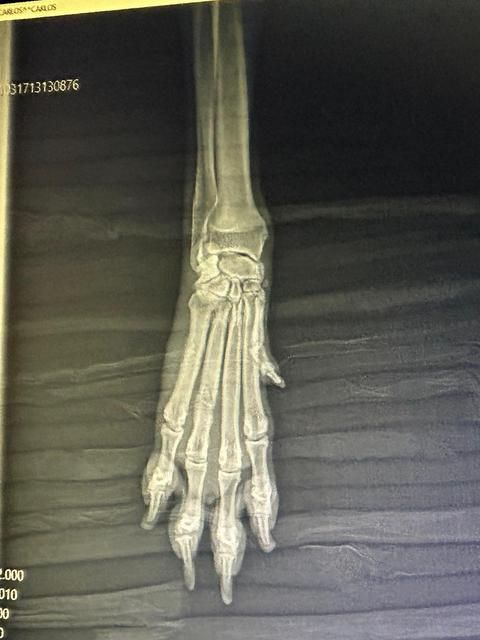

In der Tierklinik angekommen, wurde sie gründlich untersucht. Sie war stark entkräftet, ausgehungert und hat einige gebrochene Zehen. Glücklicherweise scheint es so, dass ihre Pfoten ohne Operation heilen können – sie muss jedoch eine Weile ruhig im Käfig gehalten werden, damit alles wieder richtig zusammenwächst.